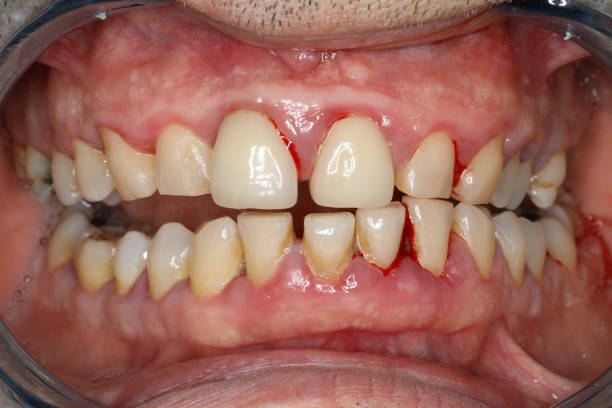

歯周病は、ほとんど痛みなく進行する病気です。

そのため、自覚症状がないまま進み、気づいた時には歯を支える骨が溶けているというケースも少なくありません。

・歯ぐきから血が出る

これらは、歯周病の初期サインであることが多く、本人が気づかないうちに進行していきます。そして最終的には40代から主に全身の様々な疾患を起こしにかかる怖い病気です。

当院では、歯周病を正しく把握するために、歯周ポケットに器具を入れて、精密検査を行っています。

・歯周ポケットの深さ

・出血の有無

・歯ぐきの炎症状態

を、すべての歯・すべての面で細かくチェックします。

見た目がきれいに見えるだけで、歯ぐきの中(歯周ポケット)では炎症が進んでいることは珍しくありません。